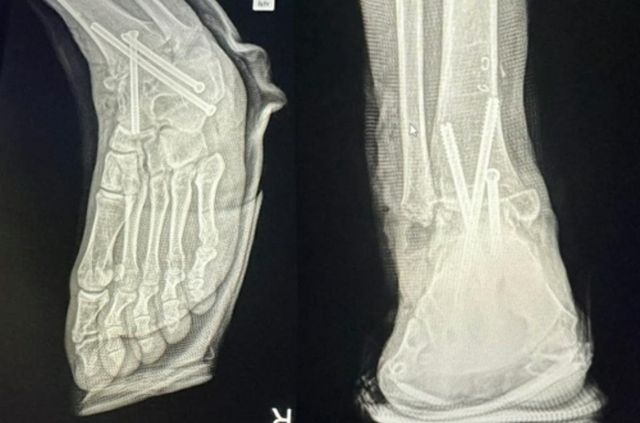

약 2시간의 수술이 끝난 뒤 마취에서 깨어난 A씨는 충격과 절망에 빠졌다. 멀쩡하던 오른 발목뼈가 잘리고 철심 3개가 박혀 있었던 것이다. 그는 즉시 경찰에 신고해 의료과실 증거를 확보하고 다시 왼발 수술을 받았다.

병원 실수로 멀쩡한 발목뼈를 절단해 철심 3개를 박은 모습 / 연합뉴스

해당 병원은 그동안 A씨의 병원비를 받지 않았고 재활치료를 돕기 위해 병원 근처에 월세방도 얻어줬다. 그러나 A씨의 오른발은 과거의 온전한 모습으로 돌아갈 수 없는 것으로 전해졌다. 복숭아뼈를 잘라 여러 뼈를 철심으로 연결해 발목이 움직이지 못하도록 고정했기 때문이다. 현재는 뼈들이 다 굳어진 상태라 전으로 돌아가기 더 힘든 것으로 알려졌다.